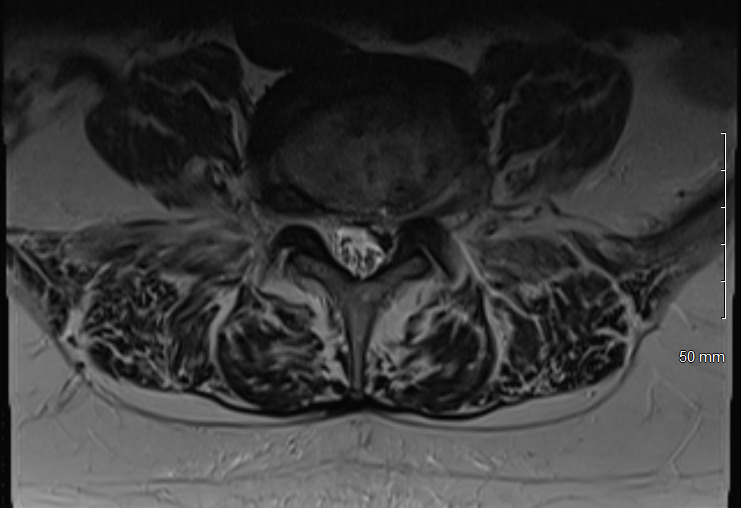

Physical examination revealed hypertonicity and tenderness in the lumbar paraspinal muscles and the left posterior hip region. He reported a pain level of 8/10 on the NPRS, reflecting both LBP and radicular symptoms. Additionally, a score of 32 out of 40 on the DVPRS indicated substantial pain-related functional impairment. A 2024 lumbar spine MRI demonstrated degenerative disc disease, arthropathy, severe left subarticular recess stenosis at L4-L5 with L5 nerve impingement, and a small left central disc extrusion at L5-S1 abutting the S1 nerve root (Figs. 1–4).

This case report documents an unexpected improvement in PLP during chiropractic treatment for LBP and radicular symptoms in a patient with a below-knee amputation. The temporary abolition of PLP reported at Visit 5, which was sustained for 2 weeks, suggests that automated lumbar long-axis distraction and myofascial release may influence the neuropathic pain pathways in amputee patients. Furthermore, lumbar distraction may reduce mechanical compression on the L5 nerve root, as seen on MRI (Figs. 1-4), potentially decreasing spinal cord hyperexcitability associated with PLP.15 Myofascial release, by addressing trigger points and muscle tension, may alter afferent input to the spinal cord, influencing pain processing.16 Chiropractic manipulation has been shown to modulate pain perception and widespread pressure sensitivity, likely through activation of descending inhibitory pathways. While these mechanisms may play a role in conditions involving central sensitization, their relevance to neuropathic pain such as PLP needs further investigation.17